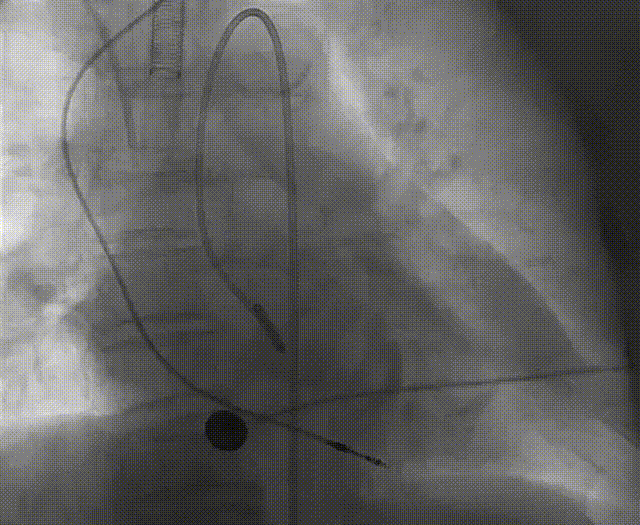

手术流程概括

22球囊扩张,无明显腰增,无造影剂泄露。

瓣膜初始零位释放,释放后位置尚可,决定完全释放。

瓣膜释放后有瓣周漏显示决定进行球囊后扩。

后扩后形态良好,瓣膜展开充分,轻微瓣周漏。